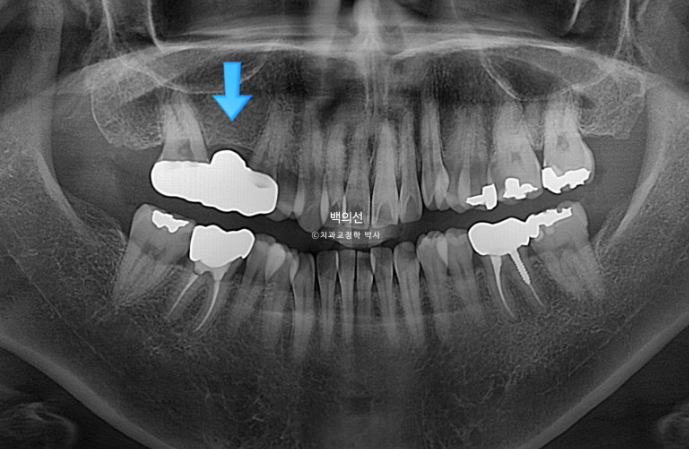

2022.12

그런데 파란 화살표 부분에 큰어금니가 하나 없습니다.

오래 전 큰어금니가 빠진 부분을 브릿지로 치료해 놓은 상태입니다.

치료의 편의성을 위해서는 작은어금니 4개 발치가 필요하나 브릿지 자체가 오래되기도 해서 파란 화살표쪽 분악은 추가적인 소구치 발치 없이 브릿지를 잘라내어 큰어금니 빈공간에 이용하기로 합니다.

그러면 작은어금니 발치갯수를 4개에서 3개로 줄일 수 뿐더라 오래전 큰어금니 빠진 자리를 임플란트 없이 교정으로 메꿀 수 있는 장점이 큽니다.